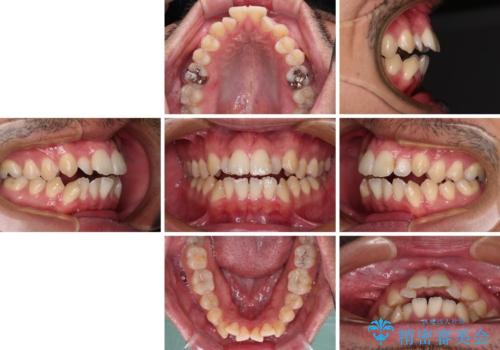

開咬とデコボコを整える インビザライン矯正治療

- 前歯の開咬と叢生を気にして来院された患者様です。

開咬の治療は、前歯を閉じるように動かすとともに、上下臼歯を圧下(骨内にめり込ませる)させることで進めて行きます。

インビザラインは臼歯の圧下を効果的に行えるため、インビザラインを用いて矯正治療を行うこととしました。また、アンカースクリューを用いて、口元の突出感の改善を図りました。

オープンバイトは舌の突出癖により誘発され、治療後も突出癖が残っている容易に後戻りしてしまいます。

治療期間を短縮するためにも、舌突出癖の改善が極めて重要となります。